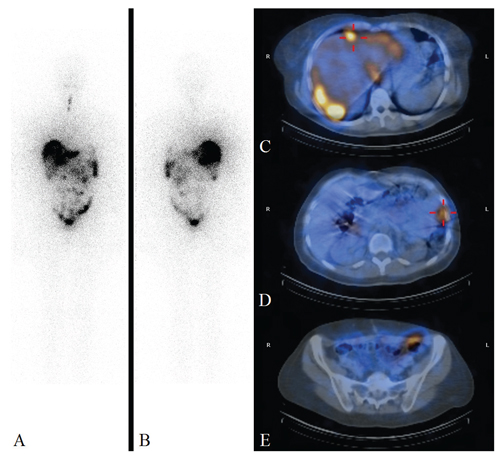

The patient was then referred to the multidisciplinary thyroid tumor board of our Institute. Workup for thyroglobulin (Tg) disclosed elevated serum values (1000 ng/ml) suspicious for persistence of disease; serum TSH, thyroid autoantibodies, FT3 and FT4 were in the normal range and consistent with a euthyroid status. Excluding two cystic areas of 4 mm in maximum diameter in the right lobe, US of the thyroid showed no other abnormalities. 18F-FDG-PET/CT scan (Figure 1) performed for disease staging revealed the presence of areas of abnormal radiopharmaceutical uptake in the liver (VII segment), presacral area and left hypochondrium (consistent with a peritoneal secondary lesion); moreover, non-specific diffuse increased radiopharmaceutical uptake was found in the spleen. Abdominal US showed peri-hepatic and intra-abdominal pelvic nodes (36 mm in max diameter), suspicious for peritoneal secondary localization. Abdominal CT confirmed all PET and US findings.

Figure 1. 18F-fluorodeoxyglucose PET images. (A) MIP image. Perihepatic (B), left hypocondrium (C) and pelvic (D) peritoneal localizations of monophasic ovarian teratoma (so-called malignant struma ovarii).